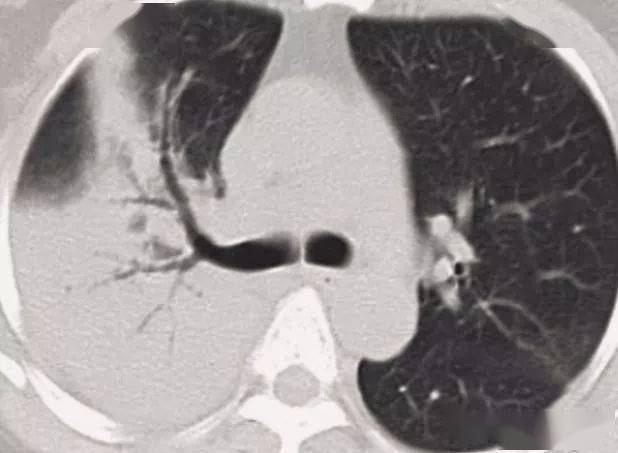

柱状支气管扩张与扫描层面垂直——"印戒征"慢性支气管炎继发柱状支

"印戒征":扩张支气管与ct扫描层面垂直时(正常同级别的肺动脉直径稍

15,"印戒征"一环状影(代表扩张的厚壁的支气管)伴有一小的软组织影

25,印戒征(支气管轨道征): 影像表现: 由一个小的圆形软组织